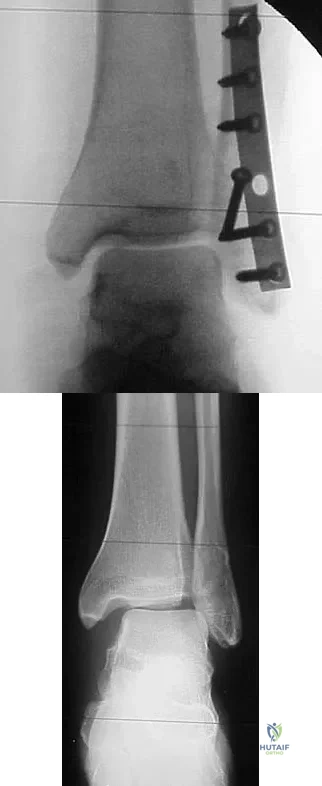

Question 16

The plate seen in Figure 48a was applied to the fracture seen in Figure 48b, and is functioning in what capacity?

Explanation